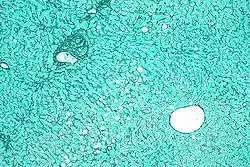

Reticular fibers, reticular fibres or reticulin is a type of fiber in connective tissue[1] composed of type III collagen secreted by reticular cells.[2] Reticular fibers crosslink to form a fine meshwork (reticulin). This network acts as a supporting mesh in soft tissues such as liver, bone marrow, and the tissues and organs of the lymphatic system.[3]

Reticular fiber is composed of one or more types of very thin and delicately woven strands of type III collagen. These strands build a highly ordered cellular network and provide a supporting network. Many of these types of collagen have been combined with carbohydrate. Thus, they react with silver stains and with periodic acid-Schiff reagent but are not demonstrated with ordinary histological stains such as those using hematoxylin. The 1953 Science article mentioned above concluded that the reticular and regular collagenous materials contains the same four sugars – galactose, glucose, mannose, and fucose – but in a much greater concentration in the reticular than in the collagenous material.

Because of their affinity for silver salts, these fibers are called argyrophilic.